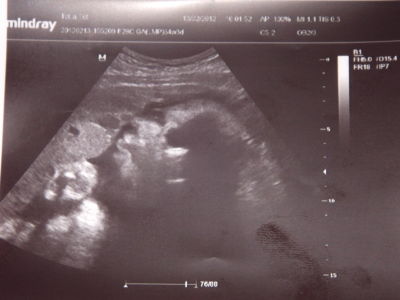

Фото УЗИ на 34 неделе